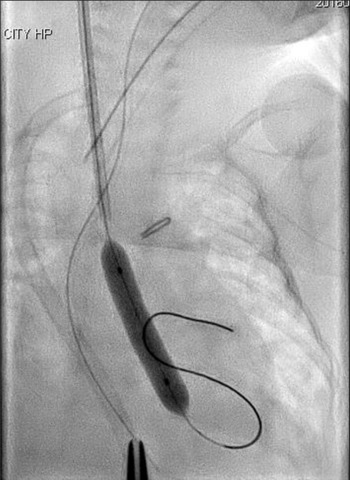

A silkworm-gut was tied on the sheath 25 mm from the tip of the sheath to prevent deep insertion, a semicircular incision was made on the common carotid artery, and a 4 Fr sheath (Terumo, Tokyo, Japan) was inserted. A 3 Fr SIM multipurpose 45° catheter (Fukuda, Tokyo, Japan) was passed through the sheath and introduced. An ascending aortography revealed an aortic valve diameter of 4.9 mm. A 4 × 20 mm TMP-Ped balloon catheter (Tokai Medical Products, Aichi, Japan) with the advantage of a short shoulder length was chosen. A 0.014′-inch Chikai guidewire (Fukuda, Tokyo, Japan) was maneuvered into the left ventricle, and the balloon catheter was positioned across the aortic valve and hand inflated immediately (Fig 2). The pressure of the ascending aorta was 55/30 mmHg, and the pull-back pressure gradient between the left ventricle and aorta was 22 mmHg. The haemodynamic condition improved significantly, and the body edema disappeared soon after this procedure. Echocardiography performed 2 days later showed no aortic valve insufficiency and a good left ventricle ejection fraction of 75%, and ultrasonography image demonstrated that there was no thrombus formation inside the right common carotid artery.

Figure 2. Balloon aortic valvuloplasty using a 4 × 20 mm TMP-Ped balloon catheter.